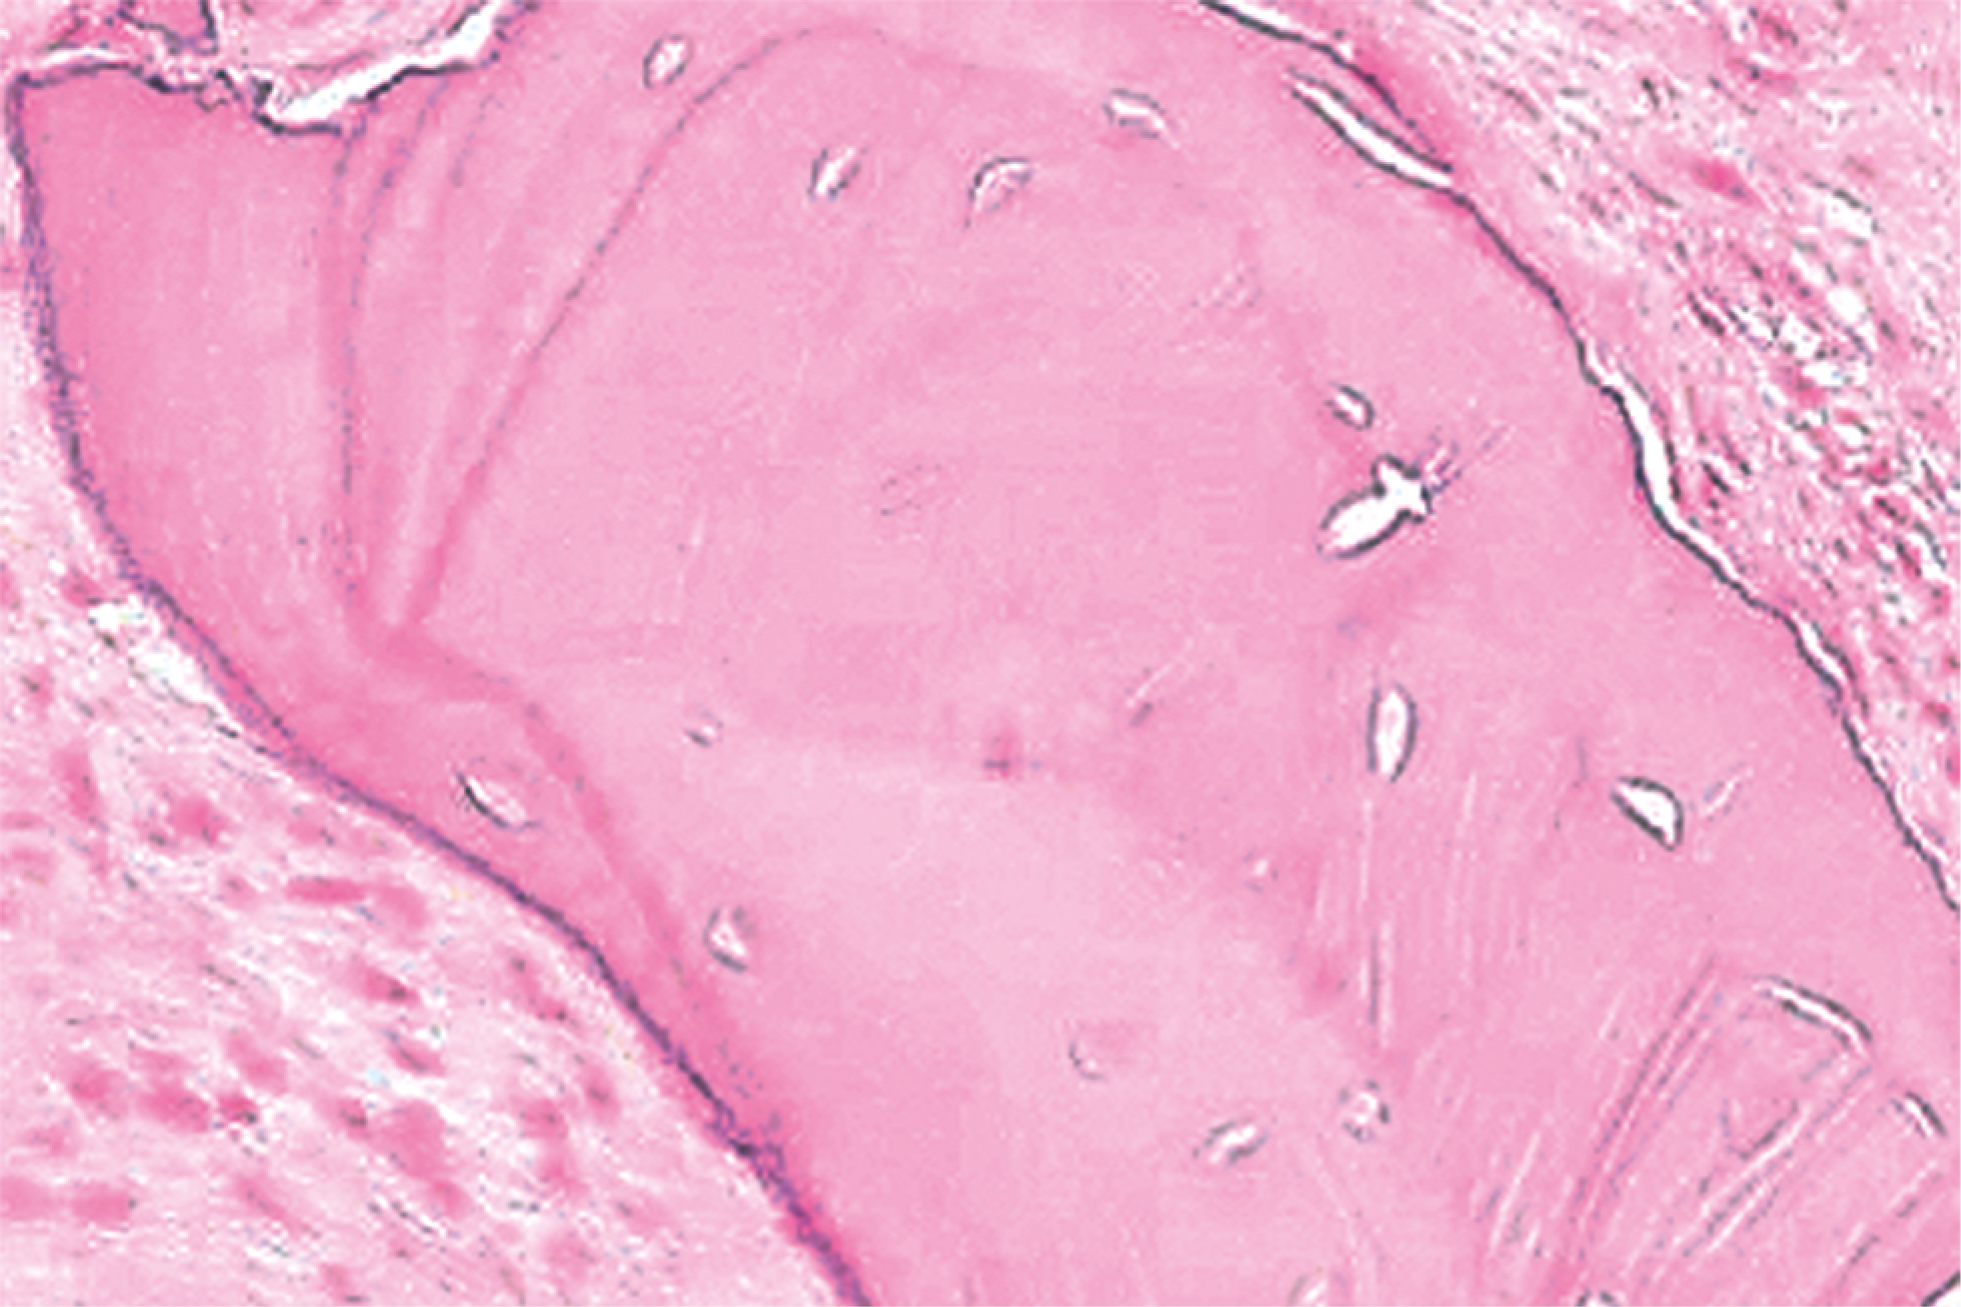

По данным гистологического исследования отмечается преобладание зрелой ламеллярной кости с активными остеобластами и преостеобластами, многоядерные остеокласты ещё обнаруживаются на границах остатков материала (рис. 2).

Рис. 2. Новообразованная костная ткань после применения комбинации костнопластических материалов «Остеоматрикс», «Биоимплант ГАП», «Биоматрикс». Окраска гематоксилином и эозином